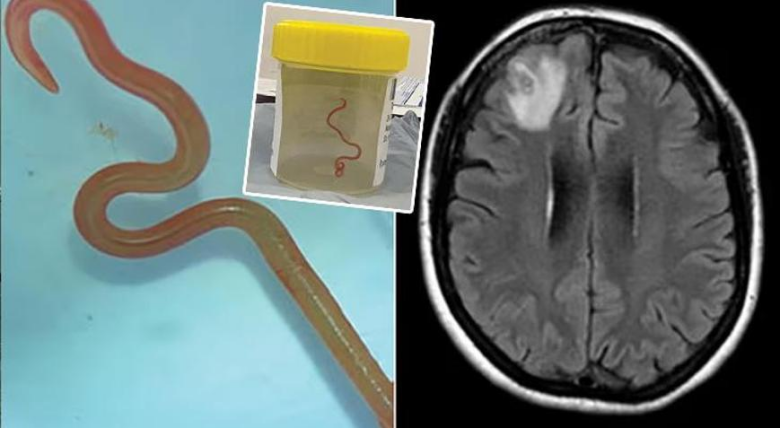

Təxminən bir il sonra qadında depressiya və unutqanlıq əlamətləri yaranıb. Həkimlər beyin MRT müayinəsi aparıblar və sağ alın payında zədələnmə aşkar ediblər. Açıq biopsiya zamanı həmin nahiyədə “sapabənzər struktur” müəyyən edilib. Araşdırma nəticəsində bunun canlı parazitar qurd, helmint olduğu məlum olub.

Qurdun uzunluğu təxminən 80 millimetr, qalınlığı isə 1 millimetr olub. Qırmızı rəngli helmint qadının beyninin alın hissəsindən cərrahi yolla çıxarılıb. Ətraf toxumalarda başqa parazit aşkarlanmayıb.